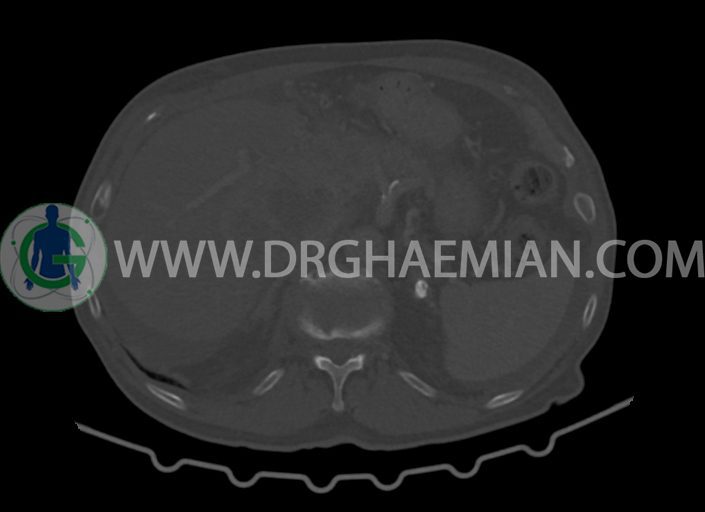

در سی تی اسکن اسپیرال شکم و لگن با کنتراست خوراکی و وریدی (مولتی دیدکتور 16 با مقاطع ظریف و بازسازی های ساژیتال و کرونال) :

-توده ی بزرگ با حدود لبوله به ابعاد 89x87x76mm در لوب چپ کبد همراه با گسترش اکستراکپسولار و

شواهد آتروفی لوب جپ کبد

-توده به قطر 33mm در سگمان 6 کبد

-توده ی هیپودنس به ابعاد 30x21mm در ورید پورت خارج کبدی مطرح کننده ی Tumor thrombosis

در ارتباط با ضایعات کبدی در درجه ی اول متاستاز مطرح است. در تشخیص افتراقی با توجه به آتروفی لوب

چپ، mass forming cholangiocarcinoma نیز مطرح می گردد.